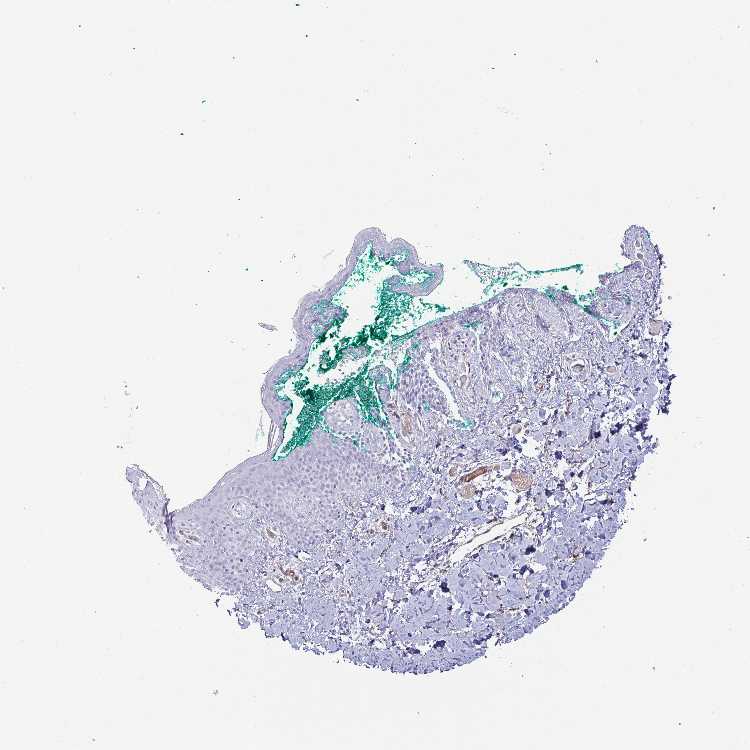

SKIN 1 - Antibody stainingi

Antibody staining in the annotated cell types in the current human tissue is reported as not detected, low, medium, or high, based on conventional immunohistochemistry profiling in selected tissues. This score is based on the combination of the staining intensity and fraction of stained cells.

Each image is clickable and will lead to virtual microscopy that enables deeper exploration of all samples and also displays staining intensity scores, fraction scores and subcellular localization as well as patient and tissue information for each sample.

Antibody HPA053772Antibody HPA058781

Langerhans Not detectedNot detected

Fibroblasts Not detectedNot detected

Keratinocytes Not detectedNot detected

Melanocytes Not detectedNot detected